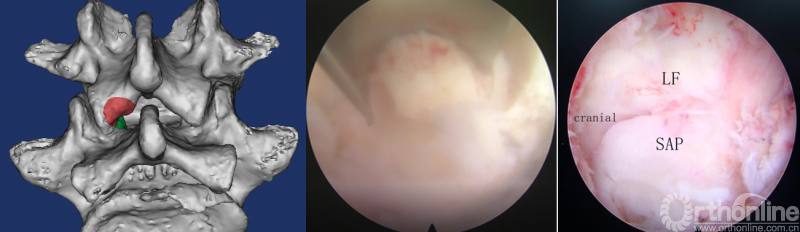

第三步“凿”:凿除部分下关节突,显露上关节突及黄韧带;

第四步“分”:分离上关节突及黄韧带;

第五步“咬”:咬除部分上关节突,显露椎间盘及神经根;